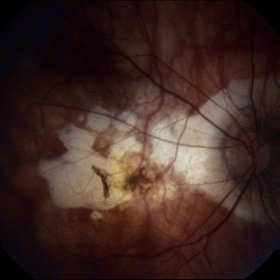

Traumatic Optic Nerve Avulsion

Jul 16 2015 by Mehul A Shah

A 21-year-old male presented to outdoor with history of blunt trauma and loss of vision on examination we found anterior segment to be normal and posterior segment had this picture.

Photographer: Mehul Shah, Drashti Netralaya

Imaging device: FF450 plus zeiss

Condition/keywords: blunt trauma, optic neuropathy